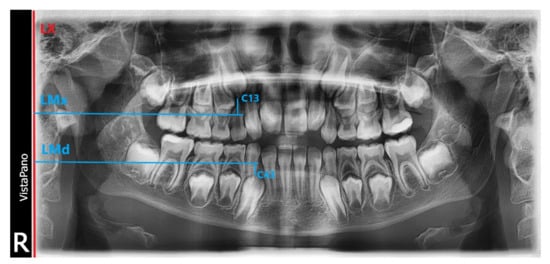

To analyze the position of the tooth buds in the lateral zones of the maxilla and mandible on the pantomographic images, customized tooth and bone parameters were determined using reference points and lines (the FDI Universal System was used to mark the teeth):

Line X—left vertical edge of the pantomographic image/LX/;

Line L Mx—perpendicular line to the X axis passing through the top of the alveolar process of the maxilla mesially from the tooth examined/LMx/;

Line LMd—the line perpendicular to the X axis passing through the apex of the mandibular alveolar process mesially from the examined tooth/LMd/;

C13—top of canine cusp 13;

C23—top of canine cusp 23;

C33—top of canine cusp 33;

C43—top of canine cusp 43;

C14—top of buccal cusp of tooth 14;

C24—top of buccal cusp of tooth 24;

C34—top of buccal cusp of tooth 34;

C44—top of buccal cusp of tooth 44;

C15—top of buccal cusp of tooth 15;

C25—top of buccal cusp of tooth 25;

C35—top of buccal cusp of tooth 35;

C45—top of buccal cusp of tooth 45.

Measurements were conducted of the distance of the points on the cusps of the permanent canines and cusps of the premolar teeth nearest to them from their perpendicular projections on the LMx line (alveolar process of the maxilla) or on the LMd line (alveolar part of the mandible). Measurements are depicted in Scheme 1. Similarly, the distance of these teeth was assessed when the tooth had already erupted. Measurements of the tooth–bone parameters were made with the Open Source ImageJ 1.52a software (LOCI University of Wisconsin) [18]. Patient data with age specified in months were entered into an MS Excel 2013 (Microsoft Excel 15.0.4420.1017) spreadsheet to allow analysis of pantomographic images to be summarized and organized [19]. Next, the tooth and bone parameters measured in ImageJ, determined on panoramic radiographs of children 6–10 years (72–120 months), were entered into the created database. On this basis, statistical data on the position of permanent tooth buds in relation to the alveolar process of the maxilla and the alveolar part of the mandible and erupted teeth were compiled. To analyze the reliability of the measurements, we used the intraclass correlation coefficient in a two-factor mixed model for absolute agreement of single measurement—ICC (intraclass correlation coefficient, two-way mixed model for absolute agreement of single measurement). For all parameters, the agreement of both measurements is statistically significant at the level of p < 0.001, and the value of the correlation coefficient r-Pearson was 0.9221–0.9977. Therefore, the reliability of the test by the absolute stability method is high.

Scheme 1. Graphical representation of measuring lines and points.